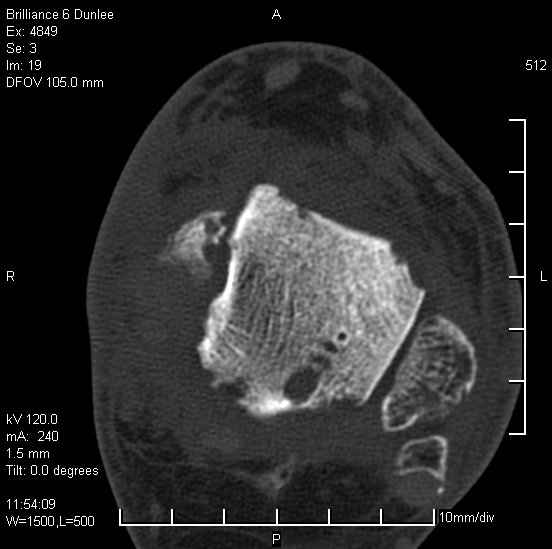

Асептический некроз таранной кости.

На лечении находится пациент 35 лет. Травма в сентябре 2008 г.- открытый вывих таранной кости

В день травмы ПХО, вправление вывиха, трансартикулярная фиксация. Рана зажила первично. С января нагрузка на конечность. С конца апреля- болевой синдром. На рентгенограммах и КТ признаки ас. некроза таранной кости, артроз подтаранного и голеностопного суставов.